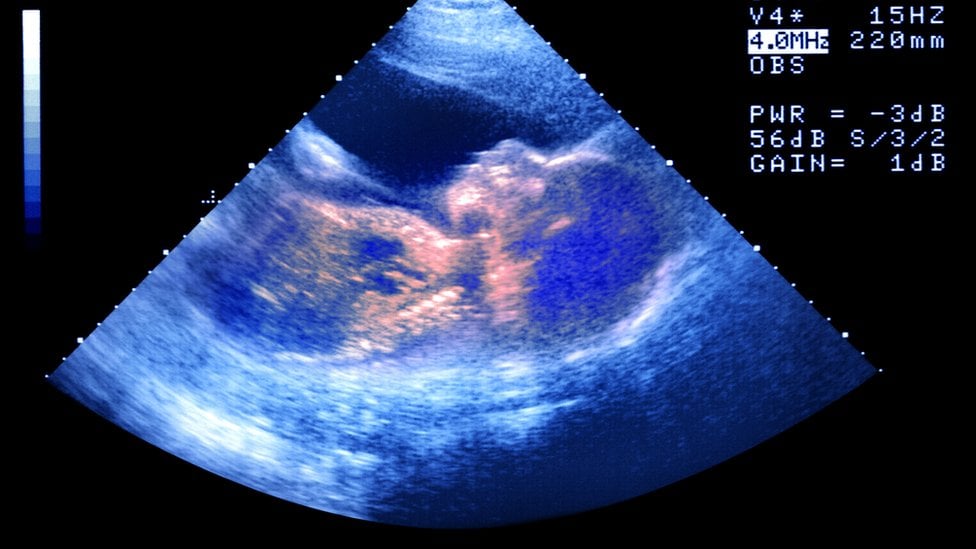

La madre de cinco hijos dijo que quería hacerse un aborto y que en el centro le dijero por teléfono que podría hacerse uno allí. Cuando llegó a su cita, dice que le aseguraron que necesitaba hacerse un ecografía. Esta mostró que estaba embarazada de mellizos.

"Me dijeron 'tienes que mirar, estos son tus bebés' y cuando finalmente giré para mirar, y vi a dos pequeños bebés en la pantalla, me limpié mi propio gel y me fui de la habitación... Eso fue demasiado para mí".

Lord criticó el uso de ecografías en los centros de orientación sobre el embarazo. Dijo: "Las ecografías son una herramienta y pueden usarse en algunas circunstancias, pero en otras pueden ser bastante intrusivas".

El uso de ecografías, añadió, puede provocar culpa en las mujeres embarazadas que están considerando abortar y por tanto pueden ser manipuladoras.